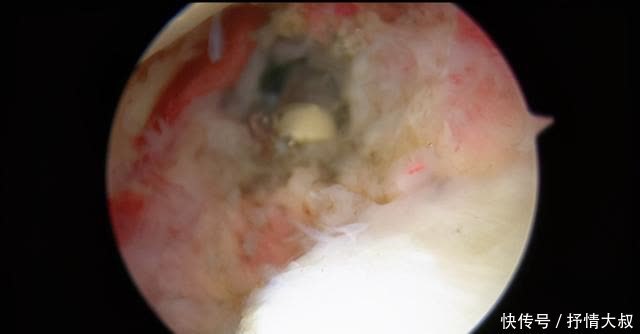

术中关节囊明显肥大(黄切头)。

关节囊360度完全松开(弯曲的红线是关节囊的一部分)